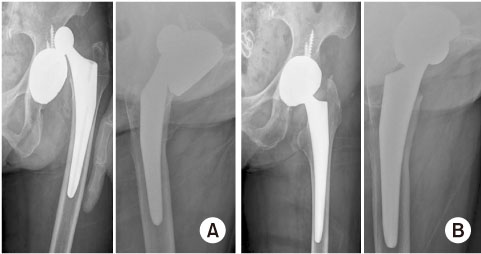

수술 2주 후 생존군에서 1예의 탈구(1.3%, 1/79)가 관찰되었으며 폐쇄성 정복이 시행되었고 보조기 착용을 통하여 보존적으로 치료에 성공하였다(Fig. 2). 생존군에서 술 후 낙상에 의한 4예의 인공삽입물 주위 골절이 발생하였으나 환자 및 보호자의 비동의로 추가적인 수술적 치료는 시행되지 않았다. 그 외의 수술 부위 주변부 감염 및 이중 이동성 컵의 폴리에틸렌 삽입물과 금속의 두 사이에서 생기는 분리 탈구는 발생하지 않았다(Table 2).

Fig. 2

(A) Anteroposterior and translateral view of an 82 years old patient after total hip arthroplasty. Two weeks after surgery, prosthesis dislocation occurred. (B) The dislocation was managed by closed reduction and abduction brace.